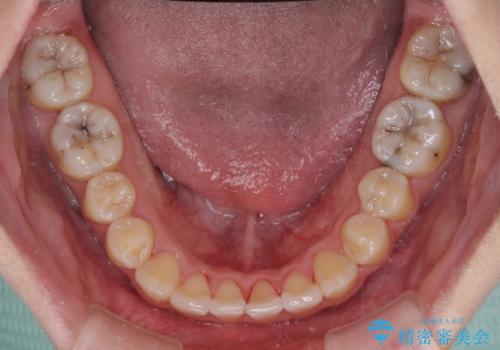

- 八重歯と叢生を気にして来院された患者様です。

上下の前歯が非接触であり、叢生や八重歯が顕著であったため、上顎左右第一小臼歯2本を抜歯して排列することとしました。

抜歯により移動量が多くなるため、ワイヤーや補助装置を活用し、その後インビザラインによる矯正治療を行うこととしました。

元々奥歯に負担のかかる咬み合わせですり減っていたため、仕上がった歯並びでも奥歯が咬んでいないように見えましたが、実際にはしっかりと咬合しており、患者様本人も咬んだ感触に違和感はないとのことでした。